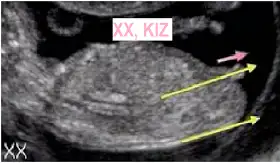

Bebeğiniz erkekmi teori doğrumu bu arada doğum yaklaşmış rabbim bir nefeste kurtarsin bebeğin izi ve siziYANLIZ BEBEK küçün nokta şeklinde olan diğer halka gibi olan yolk kesesi

Merhaba canim cvp verirsen sevinirim kuzu 8+3 ama daha kucuk yokBir tanesi ramziye göre erkek ama diğeri gözükmüyor.

Canim banada cvp verirmisin@sinemnur cnm seninkini işaretledim ancak bir önceki haftayı da görsem tam olacaktı.

Kiza benzettim benEki Görüntüle 1778998

Teori tutmadi o zaman kiz yorumlari vardi sagdamiydi soldami rabbim saglik versin insallah